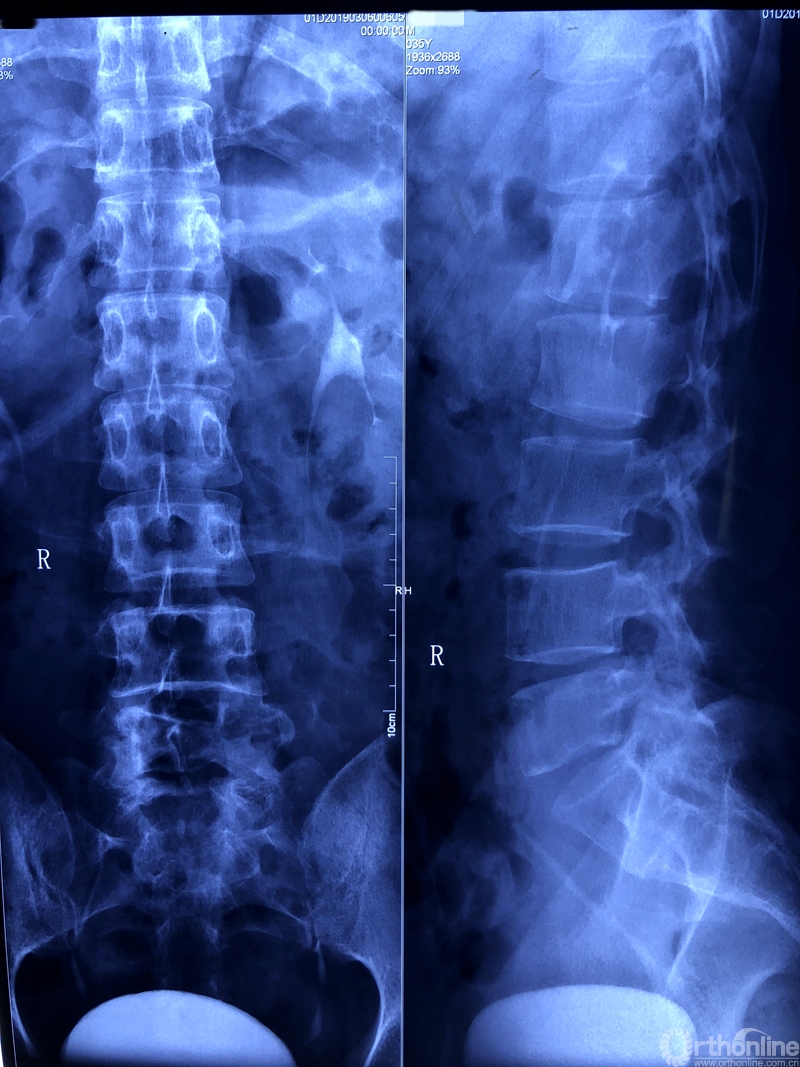

术前X线片